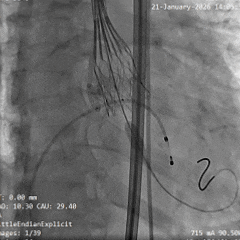

术中影像

根部造影

瓣叶钙化明显,瓣叶活动差,中度反流

直头导丝顺利跨瓣

猪尾导管测量跨瓣压差约60mmHg

20mm球囊预扩

小弯侧微腰,少量漏,左冠显影,右冠无显影

瓣膜0位初始定位释放

全展开位造影评估

瓣下约 3mm,左右冠均显影,少量反流

瓣膜稳定脱钩

无位移,无弹跳,无张力释放

根部造影评估

位置可,形态受限,可见中重度反流,左右冠均显影

20mm球囊后扩

可见瓣架底端扩开,瓣膜形态改善

最终造影可见瓣周漏,符合术前预判

超声可见左无对合缘轻度反流,整体瓣架形态较圆,左无钙化处呈“D”型,测量峰值流速为1.6m/s